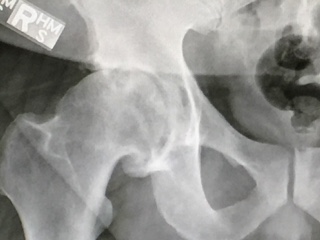

On October 9th 2017 at 8am I was wheeled into operating room #16 at Hospital for Special Surgery for my total right hip replacement. My surgeon was Dr. Allan Inglis who specializes in hip and knee replacements and in my opinion the best surgeon in the world. The surgery lasted about 3 hours from start to finish and by 5pm the day of my surgery, I was up and walking around the floor my hospital room was located on with my new hip. By 1pm the next day, I was discharged from the hospital and on my way to recovery.

After one month from getting my replacement, I am walking pain-free and cleared by Dr. Inglis to do anything I want - play golf, run, swim, work out, and best of all, I am pain-free. Given the abuse I put on my body as a young man and being a professional athlete, I will need my left hip replaced in about two years time. All I can say is Dr. Inglis should be ready for the call when I say it's time to replace hip #2. It also goes without saying that the team that made my hip is on the leading edge of innovation. Anyone considering a total hip replacement should contact HSS and ask for Dr Inglis and the hip team.